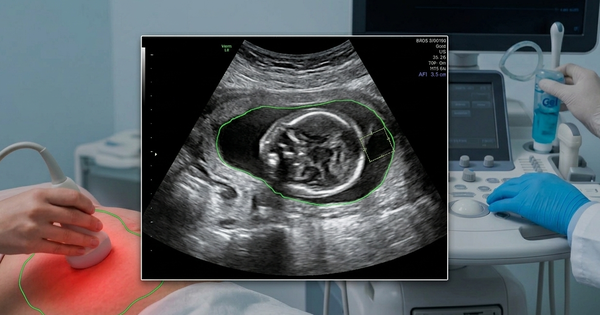

Cách bác sĩ xác định lượng nước ối thông qua siêu âm, đo chỉ số nước ối (AFI):

• Nước ối bình thường: Chỉ số AFI từ 7 – 18 cm.

• Tình trạng nước ối ít (thiểu ối): Khi chỉ số AFI thấp hơn 5 cm hoặc thể tích nước ối dưới 500 ml ở tuần thai 32 – 36.

Việc phát hiện sớm tình trạng nước ối ít đóng vai trò quyết định trong việc can thiệp kịp thời, tránh những hệ lụy đáng tiếc cho thai nhi.